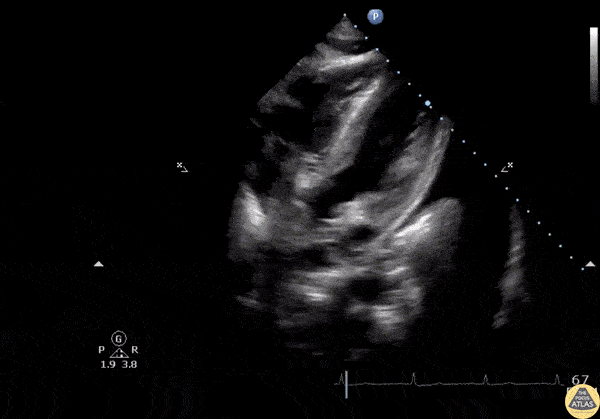

Pericardial Disease - Ascitic Fluid on Subcostal View

This subcostal view shows a patient with ascites, a small pericardial effusion, and a left sided pleural effusion. When suspecting a pericardial effusion, always ensure which side of the diaphragm the fluid presents. Image courtesy of Robert Jones DO, FACEP @RJonesSonoEM Director, Emergency Ultrasound; MetroHealth Medical Center; Professor, Case Western Reserve Medical School, Cleveland, OH View his original post here